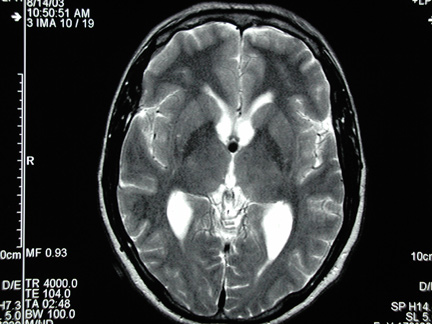

The bright spot is the cyst

The cyst is at the bottom of the butterfly shaped ventricles of fluid

Once again, it's the dark spot

Not very clear, but larger than you'd think!

Special thanks to Dr. Paul Davis for sharing these images with us!